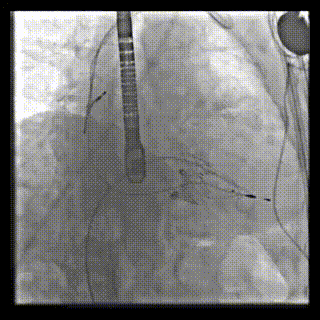

2021年12月24日,復(fù)旦大學(xué)附屬中山醫(yī)院葛均波院士團(tuán)隊(duì)成功應(yīng)用LuX-Valve Plus為一例極重度三尖瓣反流(TR)合并房顫、房缺的患者完成了經(jīng)血管三尖瓣置換術(shù),這是在前基礎(chǔ)上,本周完成的第三例經(jīng)血管三尖瓣置換手術(shù),葛均波院士、周達(dá)新教授等與心外科魏來教授、賴顥教授,心超室的潘翠珍教授、李偉教授及麻醉科的郭克芳教授共同完成了本周手術(shù),均獲得圓滿成功!患者術(shù)后超聲顯示無TR,臨床癥狀明顯改善。本周手術(shù)的成功也為LuX-Valve Plus救治性臨床研究添上了濃墨重彩的一筆。

本周三例接受LuX-Valve Plus經(jīng)血管三尖瓣置換術(shù)的患者中,第一例患者為冠狀動(dòng)脈旁路移植術(shù)+Bentall+二尖瓣成形術(shù)后;第二例患者為永久起搏器植入術(shù)后,存在跨三尖瓣導(dǎo)線;第三例患者合并房顫、房缺及左心耳封堵術(shù)后。

三例患者入院后,葛均波院士團(tuán)隊(duì)周達(dá)新教授、潘文志教授、張?jiān)床┦俊㈥惿┦考靶某业呐舜湔浣淌?、李偉教?/strong>對(duì)患者的情況進(jìn)行詳細(xì)評(píng)估和討論,最終決定為三例患者選擇LuX-Valve Plus40mm、50mm和50mm型號(hào)的瓣膜進(jìn)行手術(shù)治療。手術(shù)后即刻拔除氣管插管,術(shù)后患者三尖瓣反流癥狀得到顯著改善,復(fù)查心超結(jié)果顯示人工三尖瓣瓣膜支架固定穩(wěn)定,瓣葉關(guān)閉形態(tài)未見異常,未見明顯反流。